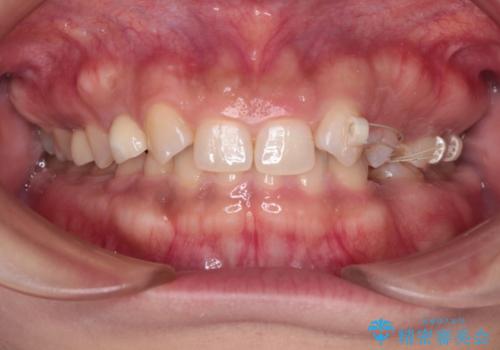

- 後続永久歯が欠損した患者様です。

矯正治療にて歯並びを改善したのち、インプラントにて咬合回復を行う治療計画としました。

捻転が強い部分だけはワイヤーの部分矯正で対応しております。